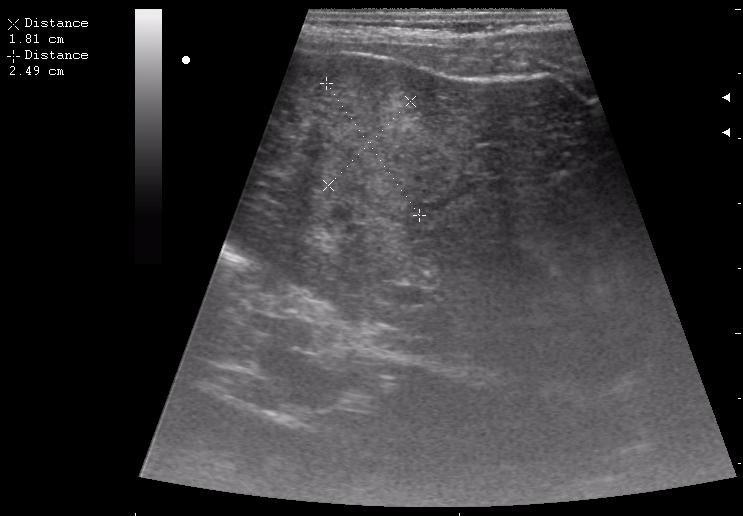

наезд большой черной Прады на маленькую (13кг) 5-летнюю девочку.

получает Медаксон, рабочая версия - изменение желчного пузыря вследствии травмы (шепотом - рекомендация хирургу сменить антибиотик)

сегодня был селезёночный день.